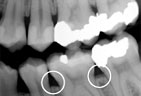

Gum disease is usually caused by plaque, a sticky film of bacteria that constantly forms on teeth. If plaque is not removed with thorough daily brushing and cleaning between teeth, gums become irritated and inflamed. The irritated gum tissue can separate from the teeth and form spaces called pockets. Bacteria move into the pockets where they continue to promote irritation. Left untreated, the process can continue until the bone and other tooth-supporting tissues are destroyed. The early stage of periodontal disease is called gingivitis. It often results in gums that are red and swollen and may bleed easily.

Gingivitis Gingivitis

(bleeding gums)

Periodontitis Periodontitis

Advanced Periodontitis Advanced Periodontitis